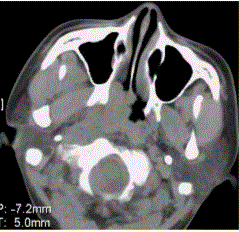

问题 患者男,45岁,鼻塞、涕中带血2周。查体颈部淋巴结增大。专科检查发现,鼻咽腔黏膜肿胀,左侧咽隐窝消失。CT表现如下图。 为明确诊断,应首选的检查为

选项 A.X线平片 B.CT检查 C.MRI D.DSA E.鼻咽活检 F.实验室检查

答案 E